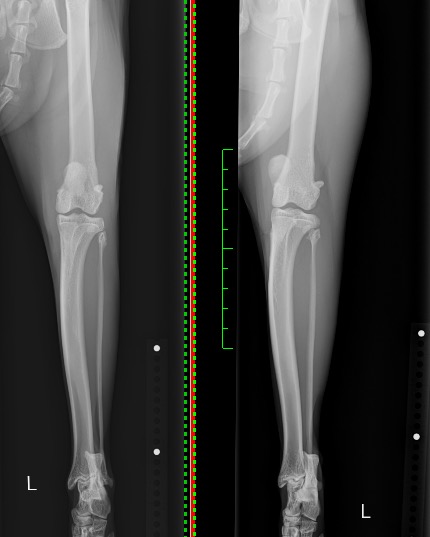

術前(右)・術後(左)のX線写真を比べると、術後では膝蓋骨がしっかりと大腿骨の真ん中に位置し、脱臼が整復されているのがお分かりいただけるかと思います。

術後の経過は良好であり、今では跛行も見られなくなっています。